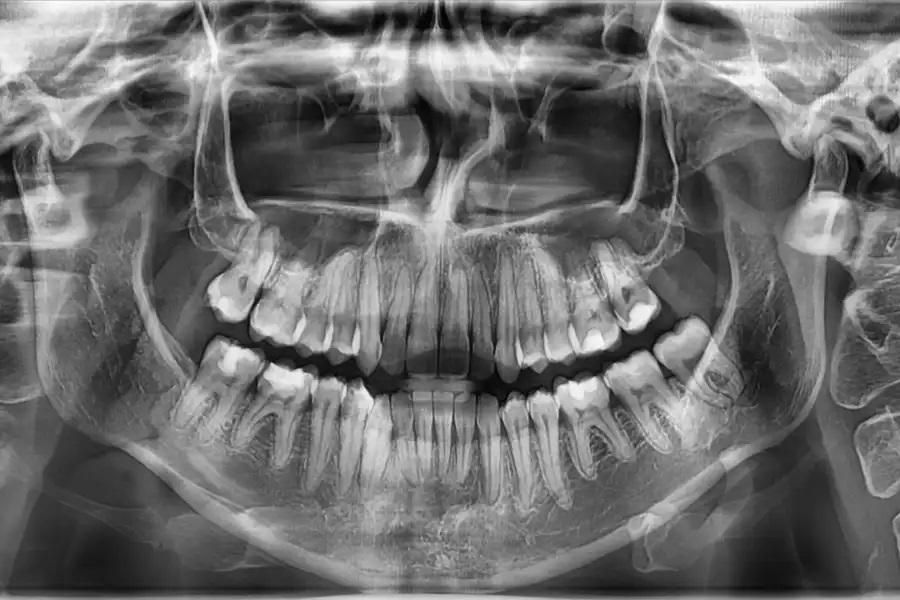

Повторная оценка по данным панорамной рентгенографии и цефалометрии используется для подтверждения интрузии боковых зубов без резорбции корней или изменений в области пазух, улучшения наклона верхних резцов в пределах костной ткани, изменений профиля губ, соответствующих авторотации пр. ч. с., и благоприятных скелетных параметров. (фото 17 – 20)

Фото 17. Панорамная рентгенограмма до лечения. Базовое изображение, демонстрирующее исходные дентоальвеолярные взаимоотношения. В области премоляров и моляров отмечается нормальный уровень краевой кости и прикрепления, служащий ориентиром для последующего сравнения.